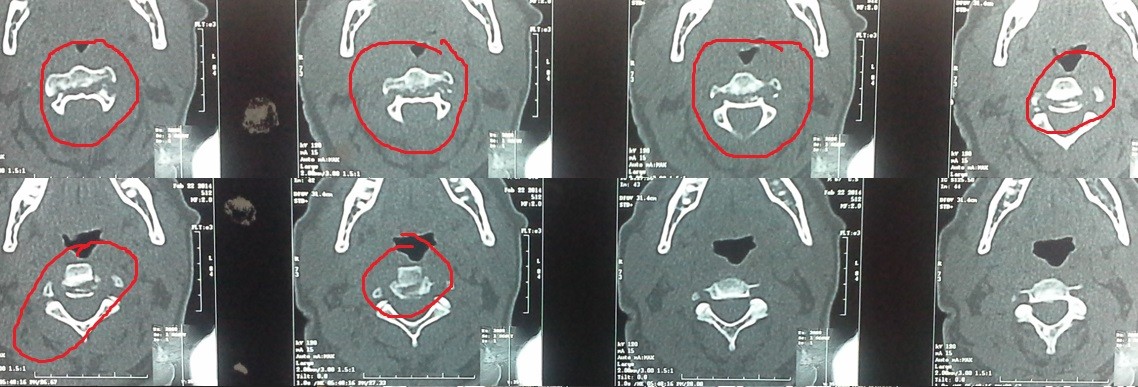

fracture of the second cervical vertebra with displacement between the second and third cervical